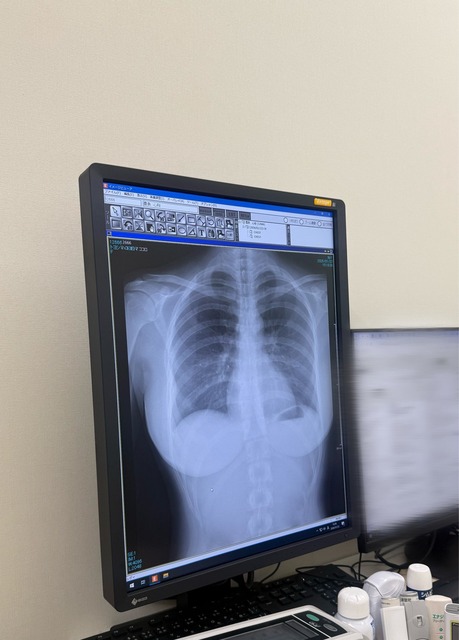

背骨大丈夫なん?